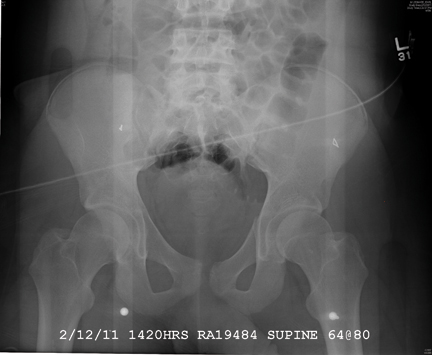

A 19-year-old man is transferred to your facility for injuries he sustained in a motor vehicle collision. He was an unrestrained passenger in a vehicle that went out of control and left the road. At the outside facility, he was found to have a chest injury and a pneumothorax, resulting in his transfer for tertiary level care. On arrival, he is complaining of some chest wall pain, but also states that his hips—especially the left one—are causing quite a bit of discomfort. His medical history is unremarkable except for sickle cell trait. Primary survey reveals stable vital signs and no obvious injury. On closer examination, with stress on his pelvis, he does complain of localized pain on the left side. Radiograph of the pelvis is obtained. What is your impression?

There is a cortical irregularity at the medial margin of the left iliac bone at the level of the acetabulum, strongly suggestive of a fracture. In addition, there may be a nondisplaced fracture within the superior/inferior rami on the left.

CT was recommended to further define these areas (and was already pending to evaluate the patient’s abdomen). Fortunately, there were no fractures within the hip joint, just the nondisplaced rami fracture.